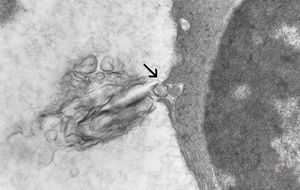

M,41y. | hairy cell leukemia - spleen - ribosome-lamella complex in tricholeukocyte